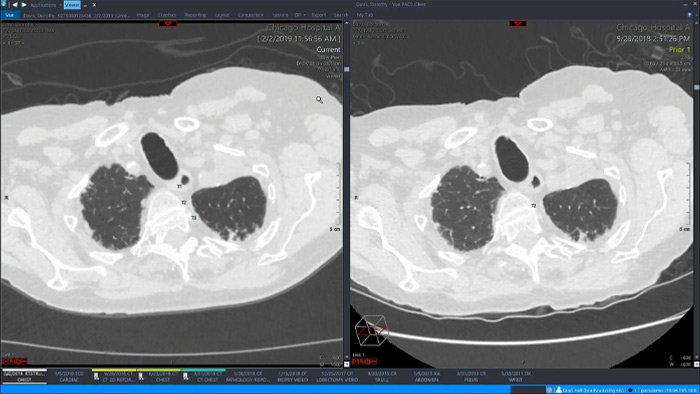

Let’s take a look at some of the immediate benefits of a unified approach. A single, unified workspace for radiology would incorporate advanced 3D post-processing and image distribution capabilities, opened in an additional viewer tab for ease.

A unified workspace would mean that users can easily launch the relevant analysis tools from among the 70+ advanced applications available across multiple clinical domains. Artificial Intelligence can play a role by automating tasks and workflows, predicting usage patterns.

An all-in-one workspace, fully integrated with the enterprise imaging platform and embedded in the diagnostic viewer, offers simple, efficient access to all needed tools across clinical domains. One-click access to advanced visualization tools – such as virtual colonoscopy, 3D processing, and spectral imaging – allows for efficient interpretation and supports diagnostic confidence.

Provides a single workspace with relevant tools for confident reading and insightful reporting, improving workflow and productivity by using embedded native 3D functionality and multimedia reporting.

Offers advanced visualization with a robust set of tools for AI-assisted quantitative assessment and automatic results generation.